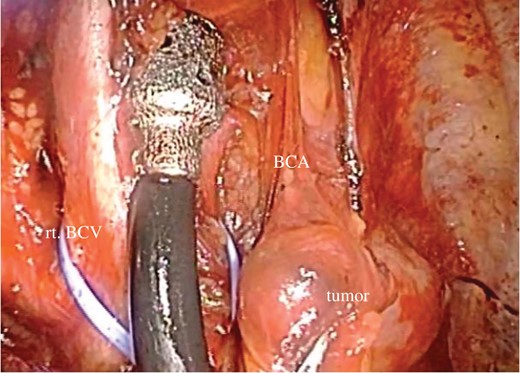

Here, we report a case of primary hyperparathyroidism due to a mediastinal parathyroid adenoma that was managed successfully by thoracoscopic resection. In this case, detailed preoperative information and magnified visual fields through thoracoscopy led to correct tumor identification during surgery, despite dense adhesions due to pleurisy. Thus, VATS resection should be the recommended treatment for functioning mediastinal parathyroid adenoma.

In general, surgical approach for mediastinal tumor depends on its location and extension, including cervical approach, thoracotomy, and median sternotomy. Thoracoscopy provides magnified visual fields with small skin incision, which is especially useful for localization of small nodules [6, 7].